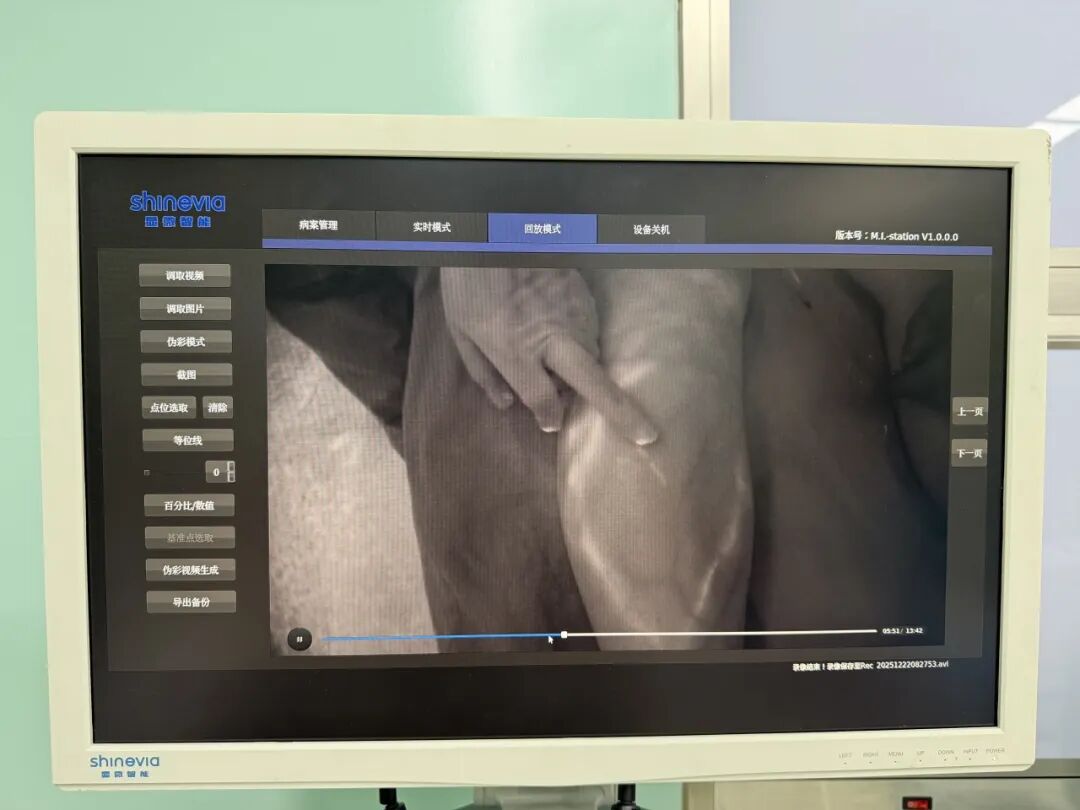

SUMMARY 内容概述: 对于许多肿瘤术后或因其他原因出现肢体肿胀的患者而言,肢体淋巴水肿不仅是身体上的负担,更是心理上的重压。近日,市二院显微功能重建外科贾长军、张微微主任团队,在国家级著名显微外科专家郑晓菊教授指导下,再次通过“CDT+LVA”综合治疗方案,为一位深受肢体淋巴水肿困扰的患者解除了病痛。 案例回顾:水肿困扰,一朝得解 近期,一位宫颈癌术后十年的女士,因双腿肿胀、紧绷、行走困难,在多家医院尝试治疗效果有限后,慕名来院求诊。显微功能重建外科贾长军、张微微主任团队接诊后,经过详细检查确诊其为“下肢淋巴水肿”,并为她量身定制了个性化的“术前调理+精准LVA手术+术后CDT康复”全周期治疗方案。 ▶ 术前:CDT手法治疗+高频超声定位 术前嘱咐患者抬高患肢,由康复师实施专业手法引流消肿,配合医用压力绷带加压固定,降低围术期风险。 同时联合超声科王云霞主任团队,借助高频超声精准定位淋巴管与静脉吻合位点,规划手术路径,筑牢术前保障。 ▶ 术中:ICG荧光造影定位+LVA手术 在国家级著名显微外科专家郑晓菊教授指导下,贾长军、张微微主任团队为患者实施了超级显微外科淋巴管静脉吻合术。术中通过ICG造影清晰显示右下肢淋巴管走形,精准标记手术路径。随后在蔡司显微镜辅助下,将十余根直径在0.1~0.5毫米的淤塞淋巴管与临近小静脉进行精准吻合,重建淋巴回流通道,让滞留在组织中的淋巴液能够顺利流入静脉系统,从根源上解决淋巴液回流障碍问题。术后ICG造影确认,所有吻合口均通畅无渗漏,淋巴液顺利流向近端静脉,患者患肢肿胀较术前明显减轻,手术圆满成功。 ▶ 术后:CDT综合康复 术后启动国际公认的肢体淋巴水肿治疗“金标准”——规范化CDT综合康复,涵盖精细化手法淋巴引流、阶梯式压力绷带治疗、个体化功能锻炼指导及专业皮肤护理等多维度干预。通过协同治疗,有效促进淋巴液回流、减轻肿胀、改善肢体功能,预防皮肤感染等并发症,打造高效、短周期康复模式。 🔺术前 🔺术后第一天 经全周期“CDT+LVA”联合治疗,患者下肢肿胀减轻,沉重紧绷感消失,肢体功能恢复正常,顺利康复出院。市二院显微功能重建外科团队在国家级显微外科专家郑晓菊教授指导下,将超级显微外科技术与规范康复理念深度融合,已成功构建起肢体淋巴水肿精准诊疗体系。该项技术的成熟开展,标志着我院在肢体淋巴水肿治疗领域已达到区域领先水平。 著名专家简介 郑晓菊 主任医师 教授 西安凤城医院手足显微外科病院院长 学术任职: 国际矫形与创伤外科学会SICOT中国部显微外科学会常务委员、中国医师协会显微外科医师分会委员、中国职工技术学会显微修复技能专业委员会常务委员、中国康复医学会修复重建外科专委会淋巴学组副组长、中华医学会显微外科学分会显微修复学组委员、中国医师协会显微外科医师分会显微足踝外科专业委员会委员、《中华显微外科杂志》编委、美国手外科学会会员、陕西省保健学会手外科与显微外科专业委员会副主任委员、陕西省保健学会创面治疗与组织修复专业委员会副主任委员、陕西省医师协会手外科医师分会常务委员、西安市医学会显微外科学分会副主任委员。 专业特色: 从事显微外科工作40余年,发表SCI及国内文章30余篇,出版专著2部,主持省级科研项目4项,市区级科研项目15项,获得省、市科技进步奖6项。先后21次出访欧美及发达国家进行学术交流。 贾长军 主任医师 葫芦岛市第二人民医院骨科主任 学术任职: 中华医学会手外科学分会东北地区手外科第九届委员、中国医师协会显微外科医师分会断肢(指)再造专业第一、二届委员、中国康复医学会修复与重建外科专业委员会第二届小关节学组委员、中国老年学和老年医学学会老年骨科分会第四届委员、全国卫生产业企业管理协会骨科分会委员、辽宁省医学会手外科学分会第七届委员、辽宁省医学会运动医疗学分会第三届委员会青年委员、辽宁省医师协会骨科医师分会第一届委员会委员、辽宁省医师协会创伤医师分会第一届委员、葫芦岛市医学会显微外科学分会第一届委员会主任委员、葫芦岛市医学会慢性创面外科修复学会第一届主任委员、葫芦岛市医学会骨科学分会第一届副主任委员 专业特色: 率先在我市开展机器人辅助关节置换手术、超级显微外科淋巴管-静脉吻合术(LVA)治疗肢体淋巴水肿。对创伤骨折mippo(微创)治疗、关节翻修、关节镜手术、脊柱骨折、椎间孔镜间盘摘除、椎管减压术、骨肿瘤手术、各类型手指再造、断(肢)指再植、游离穿支皮瓣、先后天畸形矫形、晚期功能重建、慢性难愈性创面修复、糖尿病足等有着丰富的临床经验。 张微微 副主任医师 葫芦岛市第二人民医院骨科副主任 学术任职: 中国医师协会显微外科医护交汇学组委员、葫芦岛市医学会显微外科分会副主任委员、葫芦岛市医学会慢性创面修复外科分会副主任委员、中国老年学和老年医学学会老年骨科分会委员;全国卫生产业企业管理协会骨科分会委员、辽宁省细胞生物学会数字创面修复专委员会常务委员、辽宁省细胞生物学会数字显微外科与细胞学研究专业委员会理事、辽宁省细胞生物学会脊柱脊髓修复功能重建与细胞学研究专业委员会理事、辽宁省细胞生物学会老年骨科与细胞学研究专业委员会理事、辽宁省XB-修复重建细胞学研究与数字专委会委员、辽宁省中医药学会血液病专员委员会委员。 专业特色: 擅长显微外科、慢性难愈性创面的阶段性治疗、糖尿病足感染、痛风溃疡,感染引起的溃疡、恶性溃疡、原发性皮肤肿瘤、转移性皮肤肿瘤、放射性溃疡;各种创伤引起的创面软组织缺损、感染、脉管炎;急诊创伤骨科、断指(肢)再植、手指缺损移植再造、手外伤修复及功能重建、先天性多指矫形、皮肤软组织缺损骨外露的皮瓣移植修复、四肢周围神经损伤修复、瘢痕挛缩及功能重建,关节内骨折等。